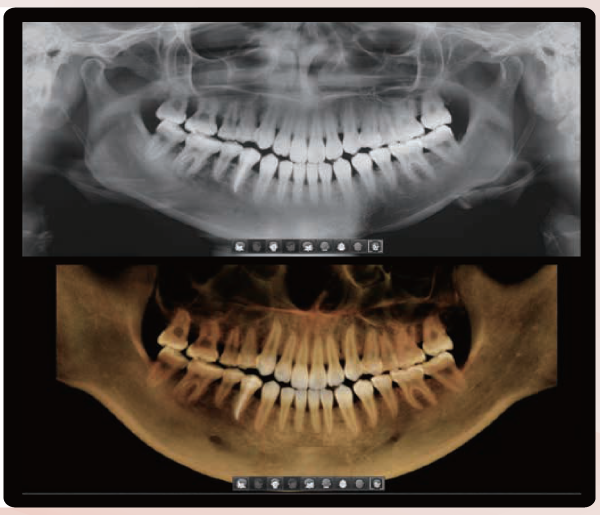

ONE SCAN, TWO IMAGES

One scan with the Smart Plus gives you not just s CT image, but also an Auto Pano image. This means, patients who require both images do not need to undergo two x-ray scans. Also, CT and Auto Pano images are displayed within one viewer.

[ 2D & 3D IMAGES IN ONE VIEWER]

Viewing 2D and 3D images together provides many benefits. There is no need to utilize two different software programs, and the one viewer feature presents a professional look for your patients.

This layout helps patients better understand the images which will eventually result in increasing acceptance rates.